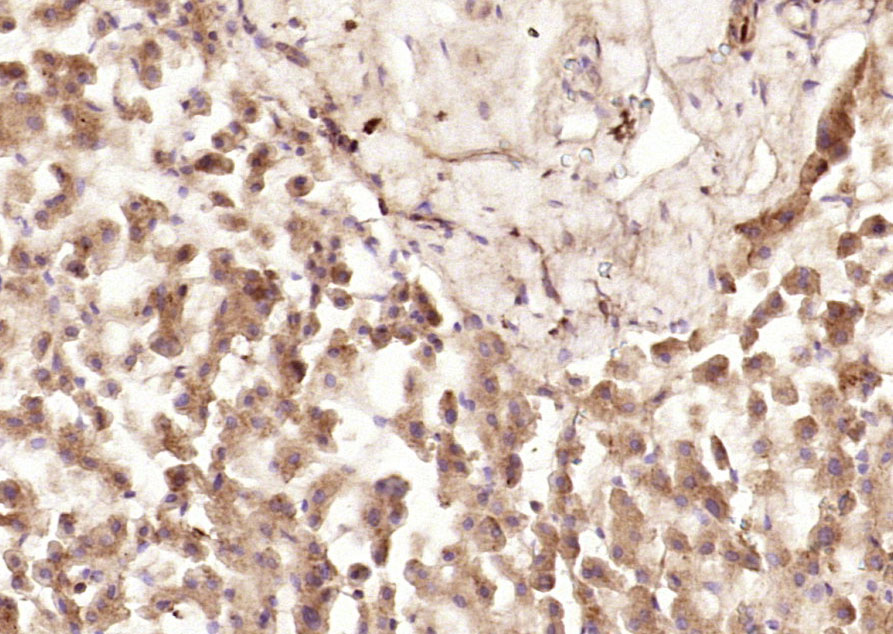

Paraformaldehyde-fixed, paraffin embedded (human colon carcinoma); Antigen retrieval by boiling in sodium citrate buffer (pH6.0) for 15min; Block endogenous peroxidase by 3% hydrogen peroxide for 20 minutes; Blocking buffer (normal goat serum) at 37°C for 30min; Antibody incubation with (SPARC) Polyclonal Antibody, Unconjugated (bs-1133R) at 1:200 overnight at 4°C, followed by operating according to SP Kit(Rabbit) (sp-0023) instructionsand DAB staining.

Paraformaldehyde-fixed, paraffin embedded (human rectal carcinoma); Antigen retrieval by boiling in sodium citrate buffer (pH6.0) for 15min; Block endogenous peroxidase by 3% hydrogen peroxide for 20 minutes; Blocking buffer (normal goat serum) at 37°C for 30min; Antibody incubation with (SPARC) Polyclonal Antibody, Unconjugated (bs-1133R) at 1:200 overnight at 4°C, followed by operating according to SP Kit(Rabbit) (sp-0023) instructionsand DAB staining.

Paraformaldehyde-fixed, paraffin embedded (Human kidney); Antigen retrieval by boiling in sodium citrate buffer (pH6.0) for 15min; Block endogenous peroxidase by 3% hydrogen peroxide for 20 minutes; Blocking buffer (normal goat serum) at 37°C for 30min; Antibody incubation with (SPARC) Polyclonal Antibody, Unconjugated (bs-1133R) at 1:200 overnight at 4°C, followed by operating according to SP Kit(Rabbit) (sp-0023) instructionsand DAB staining.

Paraformaldehyde-fixed, paraffin embedded (human liver); Antigen retrieval by boiling in sodium citrate buffer (pH6.0) for 15min; Block endogenous peroxidase by 3% hydrogen peroxide for 20 minutes; Blocking buffer (normal goat serum) at 37°C for 30min; Antibody incubation with (SPARC) Polyclonal Antibody, Unconjugated (bs-1133R) at 1:200 overnight at 4°C, followed by operating according to SP Kit(Rabbit) (sp-0023) instructionsand DAB staining.

Formalin-fixed and paraffin embedded human ovarian tissue labeled with Anti-SPARC Polyclonal Antibody, Unconjugated (bs-1133R) at 1:200 followed by conjugation to the secondary antibody and DAB staining.

Tissue/cell: human lung carcinoma; 4% Paraformaldehyde-fixed and paraffin-embedded; Antigen retrieval: citrate buffer ( 0.01M, pH 6.0 ), Boiling bathing for 15min; Block endogenous peroxidase by 3% Hydrogen peroxide for 30min; Blocking buffer (normal goat serum,C-0005) at 37℃ for 20 min; Incubation: Anti-SPARC Polyclonal Antibody, Unconjugated(bs-1133R) 1:200, overnight at 4°C, followed by conjugation to the secondary antibody(SP-0023) and DAB(C-0010) staining

Paraformaldehyde-fixed, paraffin embedded (Rat brain); Antigen retrieval by boiling in sodium citrate buffer (pH6.0) for 15min; Block endogenous peroxidase by 3% hydrogen peroxide for 20 minutes; Blocking buffer (normal goat serum) at 37°C for 30min; Antibody incubation with (SPARC) Polyclonal Antibody, Unconjugated (bs-1133R) at 1:400 overnight at 4°C, followed by operating according to SP Kit(Rabbit) (sp-0023) instructionsand DAB staining.

Paraformaldehyde-fixed, paraffin embedded (mouse brain tissue); Antigen retrieval by boiling in sodium citrate buffer (pH6.0) for 15min; Block endogenous peroxidase by 3% hydrogen peroxide for 20 minutes; Blocking buffer (normal goat serum) at 37°C for 30min; Antibody incubation with (SPARC) Polyclonal Antibody, Unconjugated (bs-1133R) at 1:400 overnight at 4°C, followed by operating according to SP Kit(Rabbit) (sp-0023) instructionsand DAB staining.